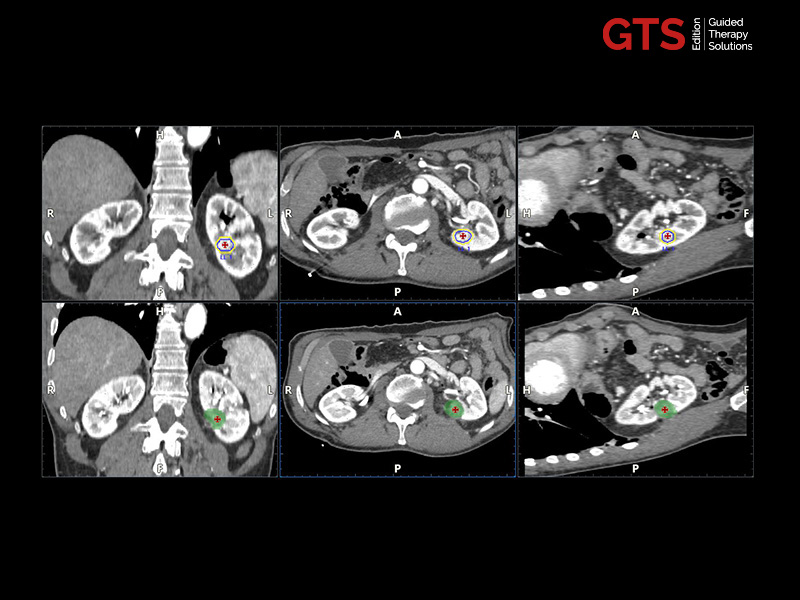

Expert users and beginners can now achieve a heightened degree of simplicity and precision by using UroFusion, Esaote’s cutting-edge fusion imaging solution that makes the most of the combination of US and MR or PET modalities.

By harnessing Augmented Insight™ (A.I.) technology, our dedicated solution enhances workflow efficiency by Automating MR Prostate Contouring & Segmentation with instant and automatic US-MR Synchronization, applied to both transperineal (TPUS) and transrectal (TRUS) prostate biopsy approaches.

Using UroFusion, clinicians will benefit from our intuitive tools to fasten the fusion procedures: the automatic prostate contouring and biopsy sample mapping are certainly the most impressive.

UroFusion seamlessly offers the ability to combine different mpMRI series, facilitating the identification of suspicious prostate lesions.

mpMRI targeting phase of PI-RADS 5 peripheral lesion